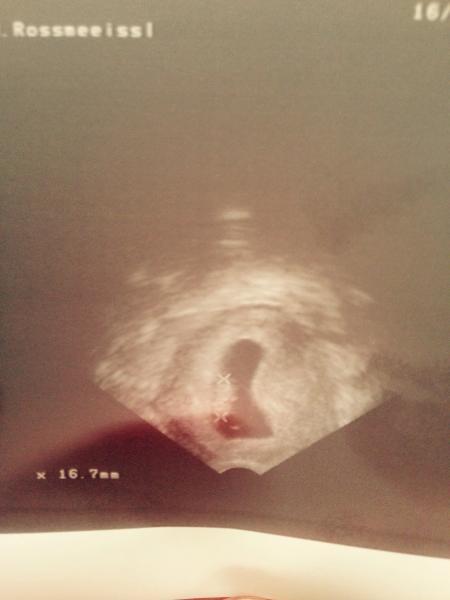

Hallo :) ich lese immer so gut wie alles mit aber schreibe nicht so oft das ständige anmelden nervt um schreiben zu können. Also ich muss sagen am anfang war ich sehr geschockt das ich beim ersten sex nach der geburt direkt wieder schwanger wurde. Aber mitlerweile freue ich mich drauf und finde es cool :) ich bin jetzt in der 10 woche und finde es wird besser mit der müdigkeit nur übergeben muss ich mich öfters als bei meinem sohn meinem babykrümel geht es bestens und deinem? Dem bauchkrümel auch hab gestern das erste ultraschallbild bekommen. Und mir gehts auch sehr gut ausser der übelkeit und dir ?